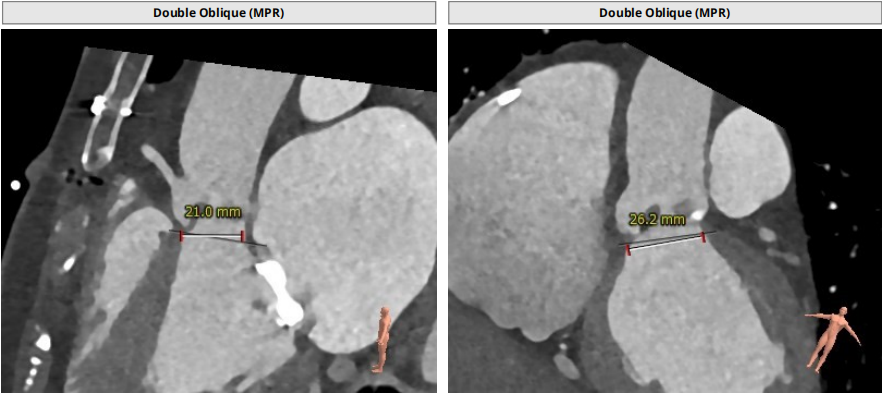

三叶瓣轻度钙化,右无可见钙化脊,瓣叶可见增厚,右冠高度可,左冠开口层面可见瓣叶,升主动脉未见明显扩张,法式窦及窦管交界稍小,两侧股动脉入路可,二尖瓣机械瓣置换术后。瓣环平均径23.7mm,LVOT26.8mm,STJ24.9mm,RCA18.4mm,LCA11.4mm。

2. STJ结构偏小且整体窦部结构不大,左冠瓣叶高度可达冠脉口,术中球囊预扩无造影剂下判断冠脉灌注情况难度大;